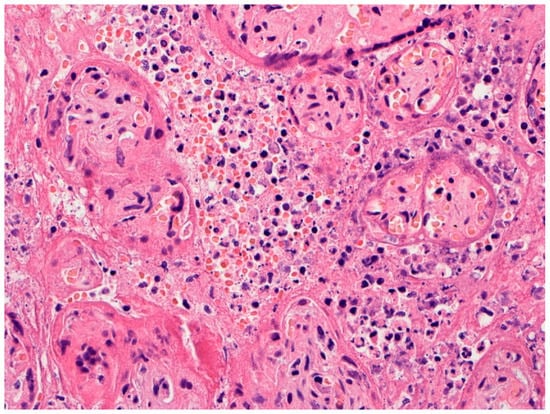

3. Placental Pathology with Evidence of Intrauterine Transplacental Maternal-Fetal COVID-19 Transmission

4. Placental Pathology with Intrauterine Fetal Demise from Mothers with COVID-19

5. Trophoblast Necrosis Together with Chronic Histiocytic Intervillositis Appears to Be a Risk Factor for Placental Infection and Maternal-Fetal Transmission of COVID-19